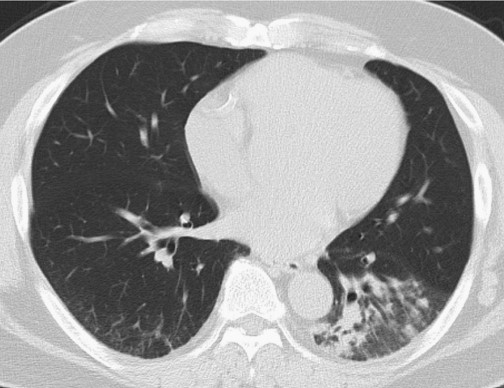

醫(yī)生試圖進(jìn)行腰椎穿刺,但因患者肥胖,手術(shù)終止。因癥狀較輕,給予患者每日小劑量氟康唑(100 mg po)治療,若效果不明顯則增加劑量。1個(gè)月后隨訪,患者表示咳嗽改善,CT顯示實(shí)變陰影明顯改善(圖3)。

圖3 高分辨率CT掃描顯示,1個(gè)月后患者左肺下葉實(shí)變改善